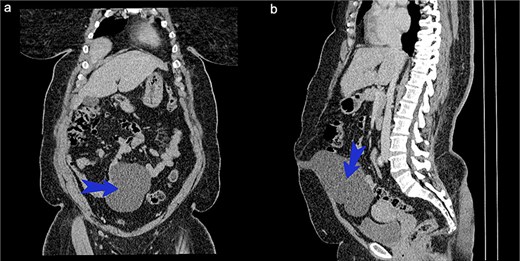

On examination, there was a well-defined lower abdominal mass measuring ~10 × 7 cm with a smooth surface. It was soft, fluctuant and mobile in the horizontal plane. No organomegaly observed. Lab investigations were all within normal limits. An abdominal CT scan (Fig. 1a and b) showed a cystic well-defined lesion posterior to the anterior abdominal wall from the level of the umbilicus to the dome of the bladder.

(a) CT scan of abdomen coronary view. (b) CT scan of abdomen sagittal view.